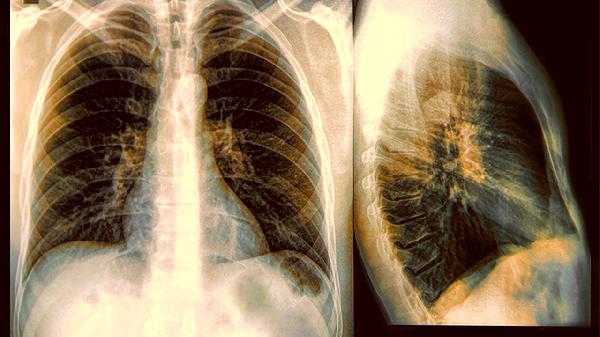

肺癌属于呼吸系统的恶性肿瘤,容易表现出咳嗽、咳痰、胸闷、胸痛的症状。肺癌早期治疗的难度比较小,但是大部分的肺癌患者在发现的时候已经属于中晚期,5年的存活率比较低。